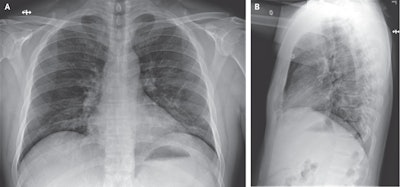

Two early cases illustrate the role x-ray played as the SARS-CoV-2 virus began spreading globally. In the first, a man from Washington state presented to an urgent care clinic on January 19 with a four-day history of cough and fever that had begun after he visited family in Wuhan. Radiographs that were initially acquired showed no abnormalities, but on his fifth day of hospitalization, x-rays showed evidence of pneumonia in the lower lobe of the left lung, and images at 10 days demonstrated basilar streaky opacities in both lungs, consistent with atypical pneumonia.

In another early case, a Vietnamese man who had traveled to Wuhan presented to a hospital upon returning home on January 22 with low-grade fever and fatigue; his chest radiographs demonstrated progressive infiltrate and consolidation in the upper lobe of the left lung.

Another study in early 2020 quantified the type of chest x-ray findings common in COVID-19 patients, with the top abnormality being bilateral rectilinear nodular opacities, found in over 52% of patients, with ground-glass opacities in over 47%. Other less common findings included pleural effusion, peribronchial thickening, and focal consolidation.

As the pandemic wore on, radiologists began to focus on the role in diagnosis and workup of COVID-19 for which radiography was best suited. Clinicians from Mount Sinai Hospital in New York City -- the site of one of the worst outbreaks early in the pandemic -- found that portable chest x-rays were most useful for predicting the prognosis of patients with known or suspected COVID-19, such as whether they would need to be hospitalized or intubated. In fact, they found that a single frontal-view chest x-ray was suitable for this purpose.